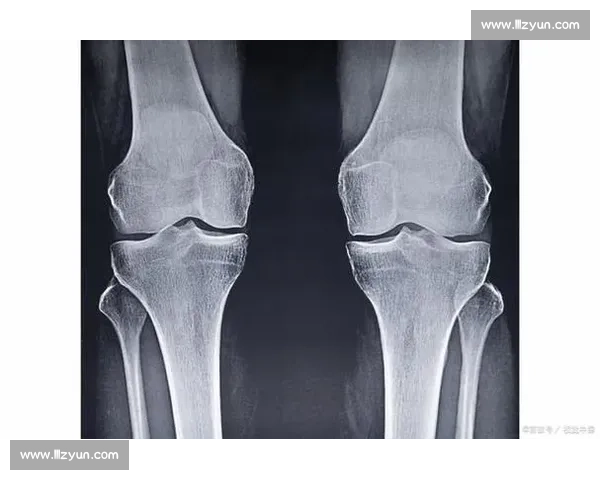

18 岁骨骺线未闭合?科学 3 招助你再长高 5cm

18 岁正值青春期尾声,身高增长虽接近尾声,但仍有部分人因骨骺线未完全闭合而保留生长潜力。通过科学干预,仍可挖掘剩余生长空间。以下是经过医学验证的实用方案: 一、营养调控:构建骨骼生长基础 ...